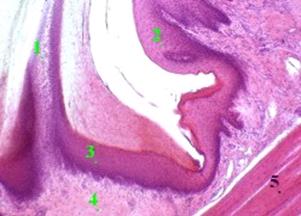

Препарат - язик. Сагітальний зріз кінчика язика

(гематоксилін-эозин)

На даному знімку зображено верхню поверхню язика і в ній -

сосочки двох типів: ниткоподібні (1) та грибоподібні (2) сосочки. Вони вкриті

багатошаровим плоским частково ороговіваючим епітелієм (3). Під цим епітелієм

розташована власна пластинка (4) слизової оболонки, яка утворена пухкою

волокнистою сполучною тканиною. У полі зору також один із м’язів язика,

утворений поперечно посмугованою м’язовою тканиною (5).